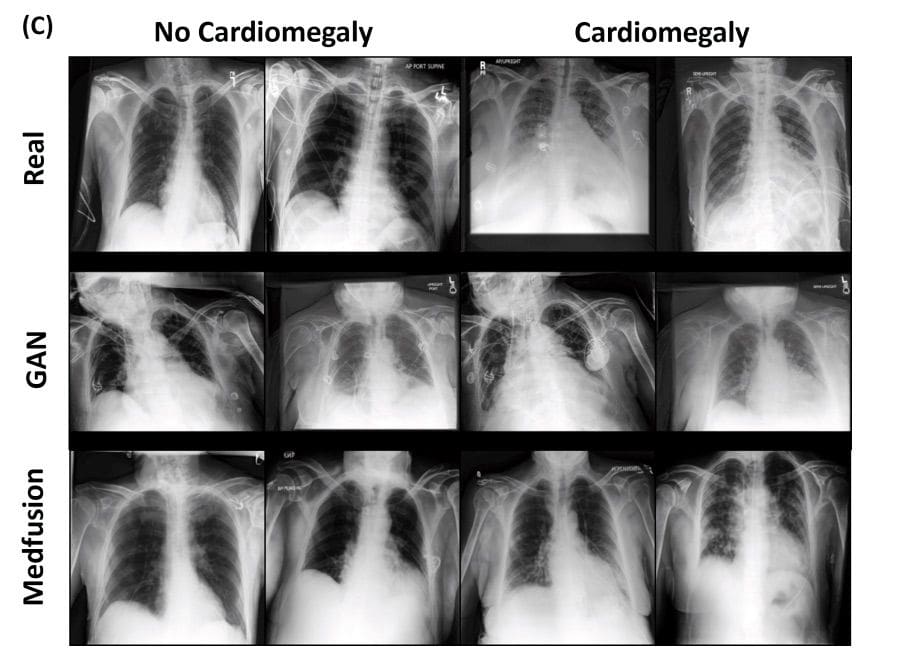

In [1] the authors present a novel approach based on Stable Diffusion [3]. The model consists of two parts: an autoencoder and a Denoising Diffusion Implicit Model (DDIM). The autoencoder compresses the image space into a latent space. During training, the latent space is decoded back to the image space. Then they use a pre-trained autoencoder to get the image to the latent space which is then diffused into Gaussian noise. A UNet model is used to denoise the latent space, and samples are generated with the DDIM. During their research they first investigated whether the autoencoder was sufficient to encode images into a compressed space and decode them back without losing medically relevant details. Then they studied whether the Stable Diffusion Model’s autoencoder, pre-trained on natural images, could be used for medical images without further training. The results showed that the Medfusion model was effective in compressing and generating images while retaining medically relevant details, and the Stable Diffusion Model’s pre-trained autoencoder could be used for medical images without the loss of any relevant details, and could outperform GANs in terms of the quality of output images. The study highlights the potential of the Medfusion model for medical image compression and generation, which could have significant implications for healthcare providers and researchers.

They explored three domains of medical data: ophthalmologic data (fundoscopic images), radiological data (chest x-rays) and histological data (whole slide images of stained tissue).